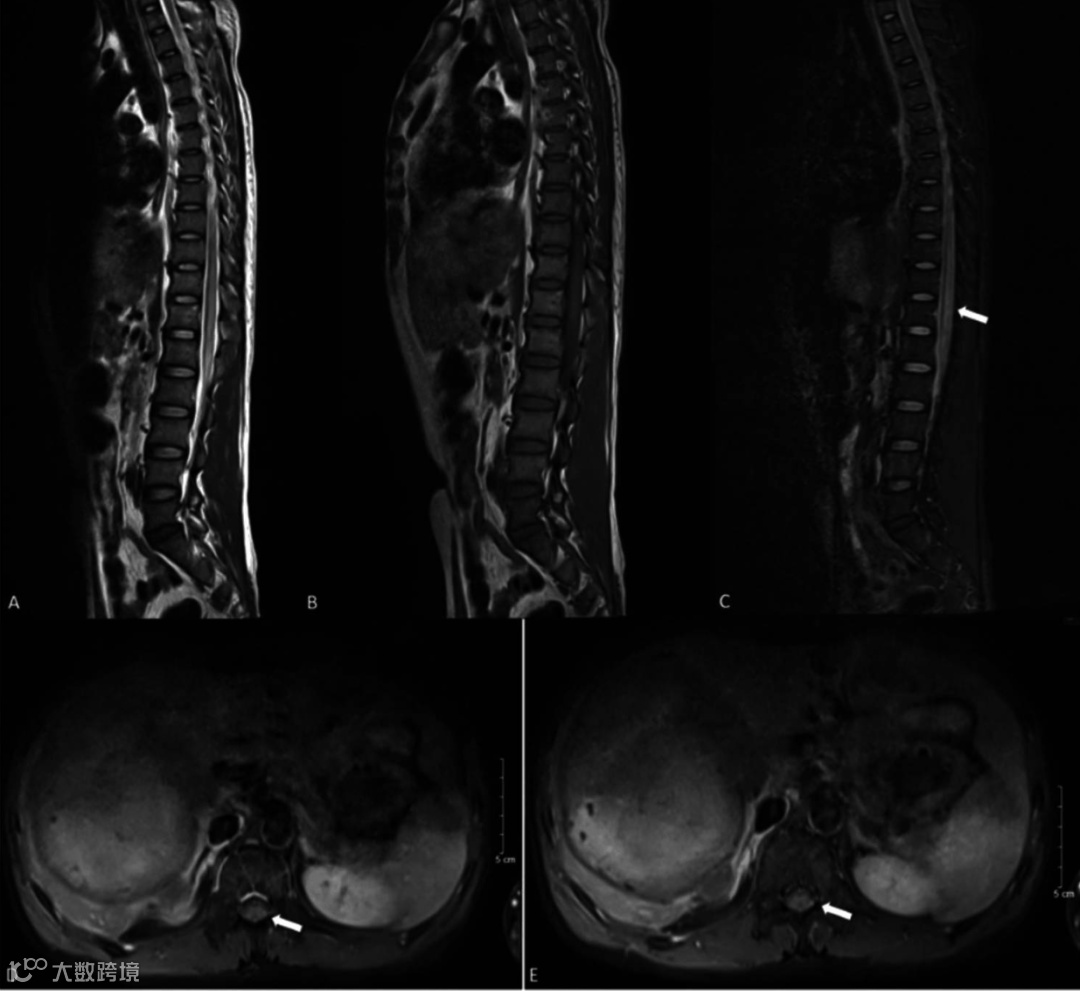

术后1小时,患者T9水平以下感觉完全丧失,右腿MRC肌力1/5级,左腿2/5级,肛门自主收缩保留。次日脊髓MRI证实T9水平缺血(图3-4)。

图3. 栓塞后次日胸腰椎MRI。A. T2W显示T9-L1水平脊髓高信号;B. T1W显示同一区域低信号;C. STIR显示高信号,提示水肿;D/E. 增强轴位像显示受累区域持续强化,提示血管炎症或充血。